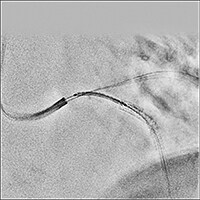

“SCORE StentView” displaying stents moving with heartbeat in a fixed position in real-time

SCORE StentView, which allows you to enhance stents and fix their position in dynamic images in real time, is exactly software developed to support PCI. It is effective to make sure the positional relationship when overlaying stents and/or when re-extending balloon in a deployed stent. In addition, the ROI setting function that enables automatic detection with multiple markers improves detection efficiency and contributes to shortening procedure time.

“SCORE StentShot” delivering High-Definition Stent Enhancement image

By emphasizing the stent and reducing image noise drastically, it improves stent visibility without increasing X-ray dose further.